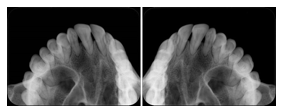

2. A patient requests cosmetic surgery to enhance their facial appearance. The case requires consultation between an orthodontist in New York and an oral surgeon in California. The cephalometric series of 2D projections constructed from a volumetric CT data set that is used for the discussion is arranged by a Structured Display for transfer between the two practitioners.

Cephalometric Series Structured Display

Figure OO-2. Cephalometric Series Structured Display